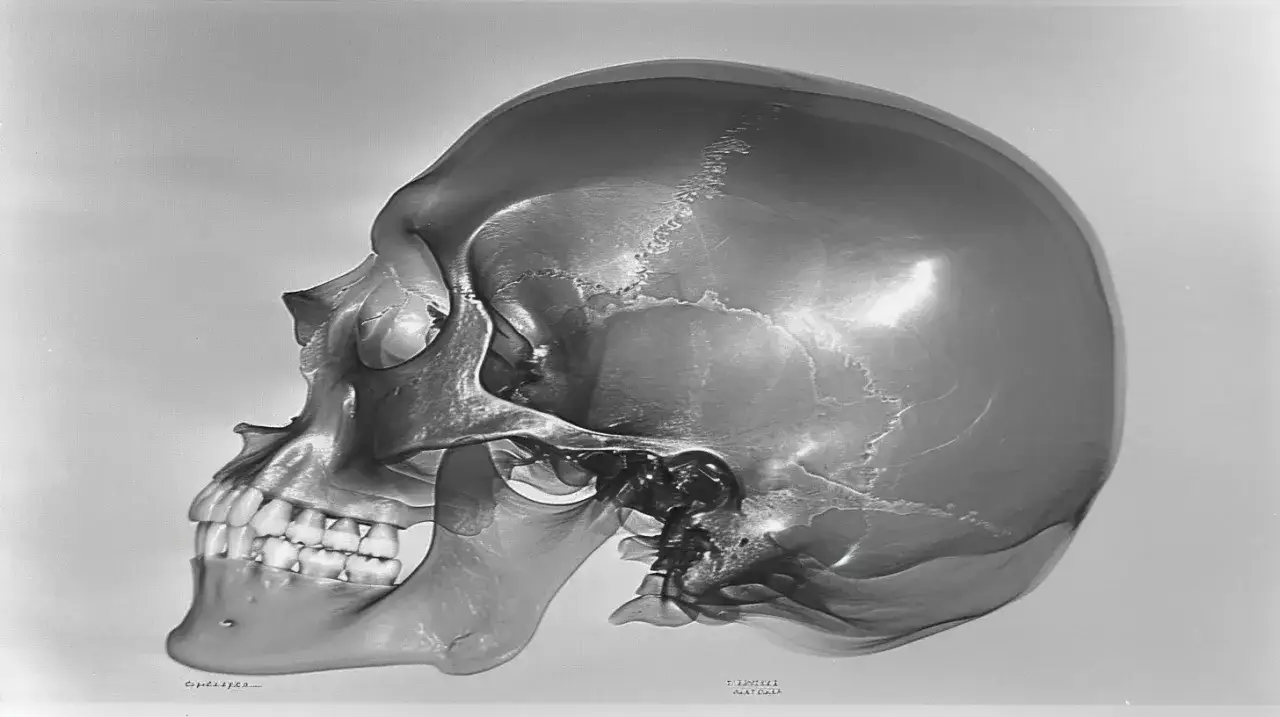

Zęby mądrości, czyli ósemki, to ostatnie zęby, które pojawiają się w jamie ustnej, zazwyczaj między 17. a 25. rokiem życia. Niestety, ich późne wyrzynanie się często następuje w warunkach ograniczonej przestrzeni, co prowadzi do licznych komplikacji. Często obserwujemy, że ósemki są częściowo lub całkowicie zatrzymane w kości, co oznacza, że nie mogą prawidłowo przebić się przez dziąsło. To z kolei sprzyja gromadzeniu się resztek pokarmowych i bakterii, prowadząc do nawracających stanów zapalnych dziąseł, znanych jako pericoronitis.

Inne typowe problemy to próchnica, która rozwija się na ósemkach, a jest niezwykle trudna do leczenia ze względu na ich położenie. Mogą one również uciskać na sąsiednie zęby, powodując ich stłoczenie, uszkodzenie, a nawet resorpcję korzeni. W skrajnych przypadkach wokół zatrzymanych ósemek mogą tworzyć się torbiele. Wszystkie te problemy są głównymi wskazaniami do ich usunięcia, zarówno ze względów bólowych, jak i profilaktycznych, aby zapobiec dalszym komplikacjom.